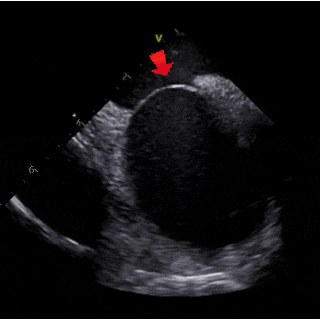

ICE下可见明显长隧道PFO

ICE下测量膨出瘤基底24mm